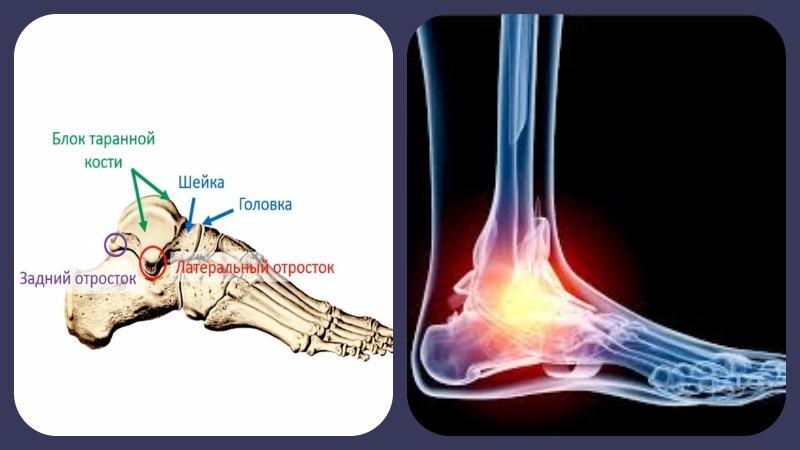

Патологический процесс чаще всего локализуется в области головки кости, в месте соединения с суставом.

Наиболее подвержены поражению крупные кости: бедренная и плечевая. Однако также часто наблюдается развитие асептического некроза таранной кости голеностопного сустава.